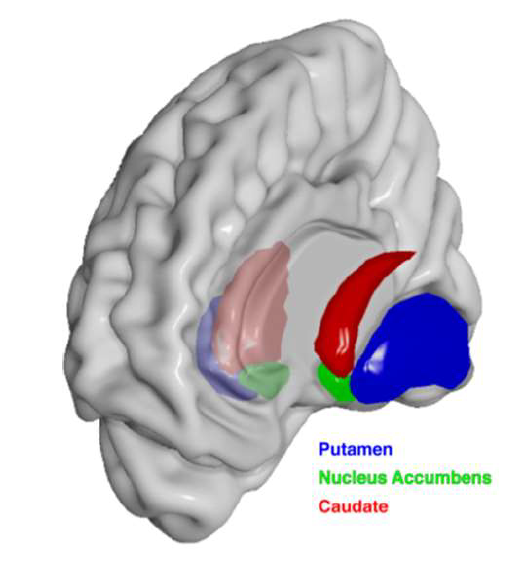

What structure is the major input to the basal ganglia?

striatum

What is the function of the nucleus accumbens (ventral striatum)?

Plays a major role in the brain's reward system, motivating us to seek pleasurable experiences.

Lesion → anhedonia